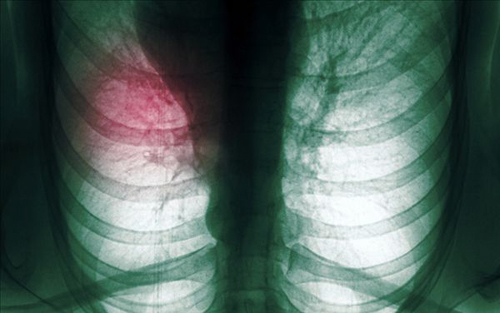

肺癌治疗在过去的40年里有了一些进展,虽然速度并不快。细胞毒性化疗联合手术治疗早期非小细胞肺癌可以提高5年生存率,联合胸部放射治疗III期非小细胞肺癌和小细胞肺癌也可以提高5年生存率。应用新的维持疗法进行化疗可以延长IV期非小细胞肺癌和小细胞肺癌的生存期,而且毒性作用很小。然而,这一提高的幅度并不大,I-III期肺癌患者5年生存率只提高了4%-5%,而IV期肺癌患者的生存期也只延长了几个月。新进展包括肿瘤驱动因子的发现和针对这些驱动因子的特殊治疗、提高缓解率和早期检测和诊断肺癌的新方法。

近期发表在《JCO》的一篇综述回顾性总结近40多年来肺癌治疗中的进展和争议,其中许多都被美国临床肿瘤学会的历史所记载。小编节选其中重要表格和肺癌治疗新方法编译如下,以飨读者。